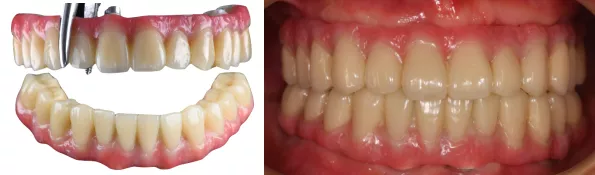

对于全口多牙缺失数年,影响功能与美观的情况下。采用个性化方案结合360数字化种植导板的方式,进行种植固定修复。充分利用原有口腔数据进行术前排牙,将排牙信息与修复设计软件结合指导虚拟设计。实现以修复为导向的种植理念。临时义齿同期恢复咬合功能。最终修复以钛支架+烤塑修复体的形式。2年随访,植体稳定且咬合无异常,修复体无崩瓷破损,效果稳定。多元素碰撞最终实现良好美学功能。

- 3个月后复查,口腔卫生良好,软组织愈合良好,临时修复体完好,叩(-)。叩诊声音清脆。X线示:种植体周未见明显异常。

- 精准二次印模,制作纯钛支架+烤塑修复体

- 戴入患者口内,调整咬合。

- 本病例修复采用纯钛支架+烤塑修复。钛支架有更好的边缘适应性,能够减小支架微移动和细菌微渗漏的发生。同时烤塑重量轻、成本低、易修补,并且弹性模量较低,可吸收咬合力,实现对种植体的保护。